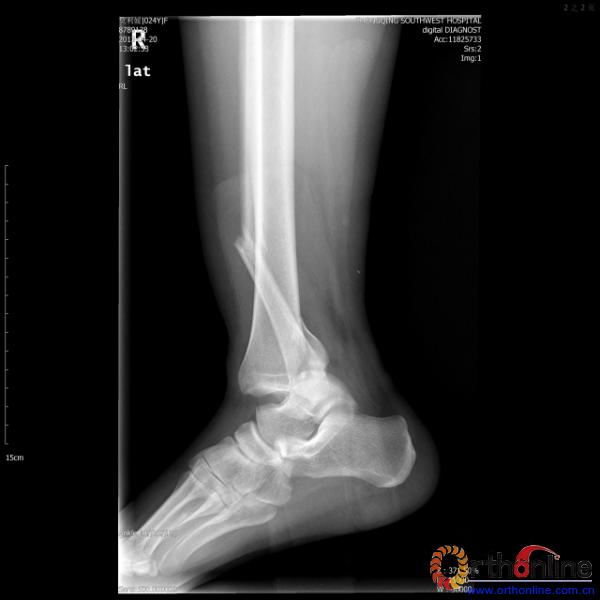

伤员和家属迅速赶到西南医院,10点关节外科段小军副教授查看伤员后急诊收入院,拍摄X片和急诊行三维CT重建检查,提示踝关节创伤严重,出现三踝骨折伴胫距关节脱位,需要急诊手术治疗。随后段教授与正在四川成都参加“汶川地震5周年灾害医学救治研讨会”的杨柳主任联系,进一步完善救治方案。地震当晚,段教授为该伤员进行急诊手术,手术顺利对复杂骨折进行了解剖复位,有效的钢板螺钉固定。术后伤员的疼痛明显缓解,复查X片,踝关节结构恢复满意。

患者术前X片(二)